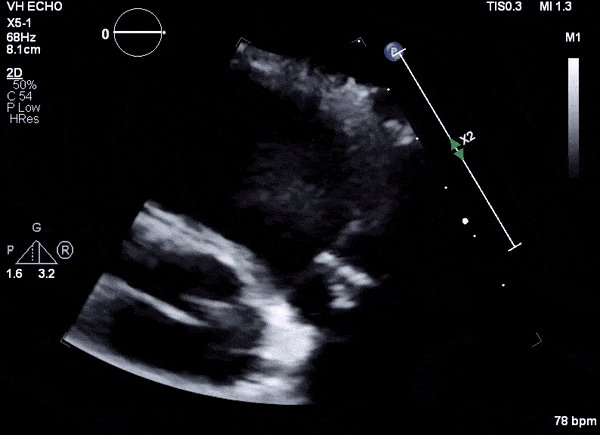

Case 1

35 year old male with history of intravenous drug use presents to hospital with fever and shortness of breath. On Auscultation there is a loud diastolic murmur best heard at the LLSB on end expiration.

Transesophageal Images